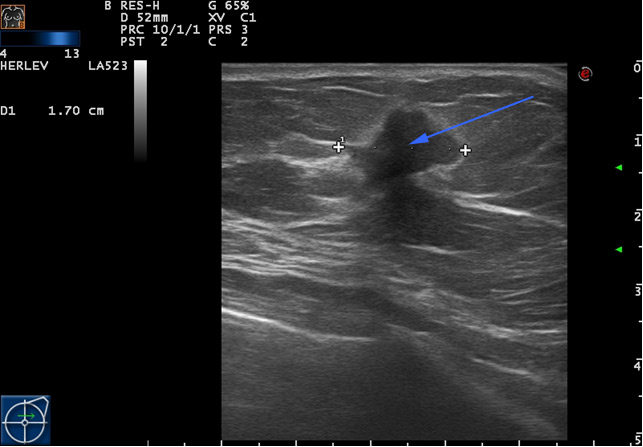

B: Forandringen undersøges også med ultralydsskanning, der også giver mistanke om kræftknude (blå pil). Som led i triplediagnostikken tager man biopsi, som siden viser sig at indholde ondartede (maligne) celler. Der tages biopsi fra knuden. Patologisk undersøgelse af prøven viser, at det er kræft.